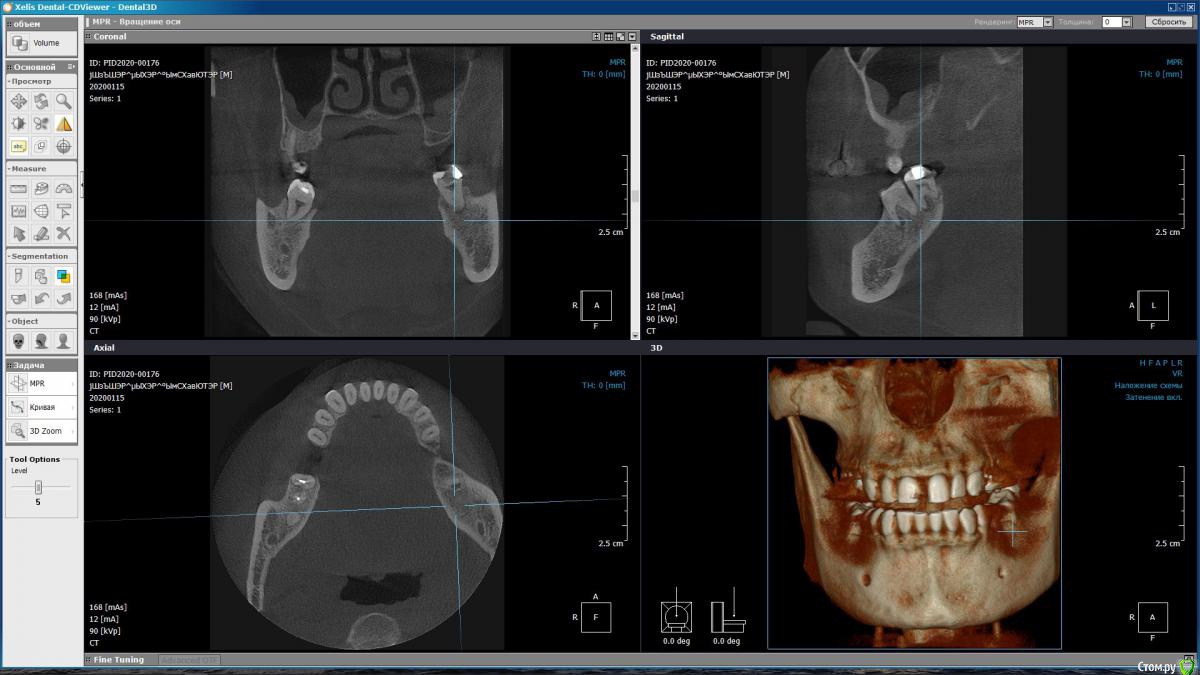

m-e-a Опубликовано 19 января, 2020 Автор Поделиться Опубликовано 19 января, 2020 (изменено) Сделала срезы как смогла, не умею я смотреть КТ Изменено 19 января, 2020 пользователем m-e-a Ссылка на комментарий

red_butler Опубликовано 19 января, 2020 Поделиться Опубликовано 19 января, 2020 На представленных срезах, показаний к удалению не увидел. Нужно смотреть очно и «крутить» Кт Ссылка на комментарий